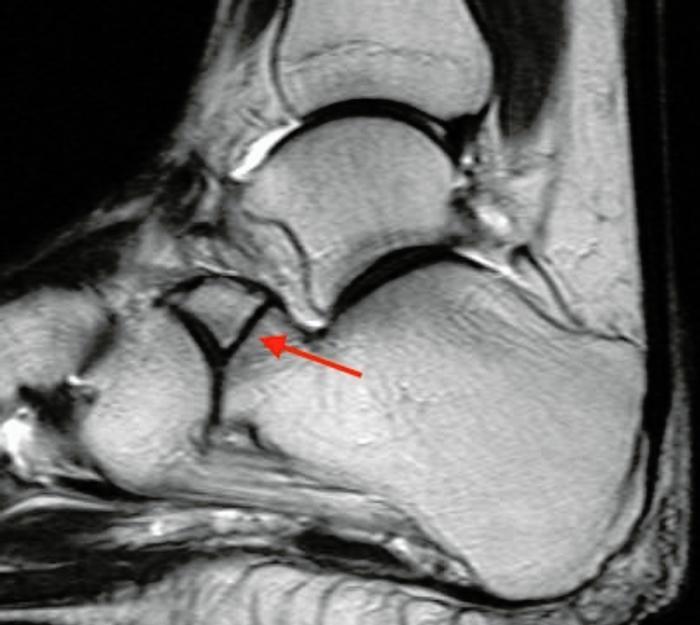

Sustentaculum tali: The sustentaculum tali is the antero-medial shelf of the calcaneum which provides structural support for the talus and includes the middle facet of the subtalar joint. The spring ligament, tibiocalcaneal and medial talocalcaneal ligaments attach to it and FHL runs in a groove under it. Isolated fractures of the sustentaculum tali are rare and are usually associated with a fall or high energy trauma, combined with a twisting movement. The patient may complain of medial hindfoot pain and have an antalgic gait. Examination will show tenderness 2-3cm below the medial malleolus.

Passive extension of the great toe may produce medial hindfoot pain, due to irritation of FHL, and subtalar joint movement will be painful and limited. They can be difficult fractures to see on standard views of the foot and are best seen on axial views of the calcaneum and then a CT scan (Figure 6 &7). It used to be thought these were extra-articular fractures which could be treated non-weight-bearing for six weeks and with early range of movement exercises, as the fractures are usually minimally displaced. It is now thought best to reduce and internally fix them. These fractures can also occur in conjunction with other trauma, such as a subtalar joint dislocation.

Fig 7.jpg

Figure 7: CT showing sustentaculum tali fracture.